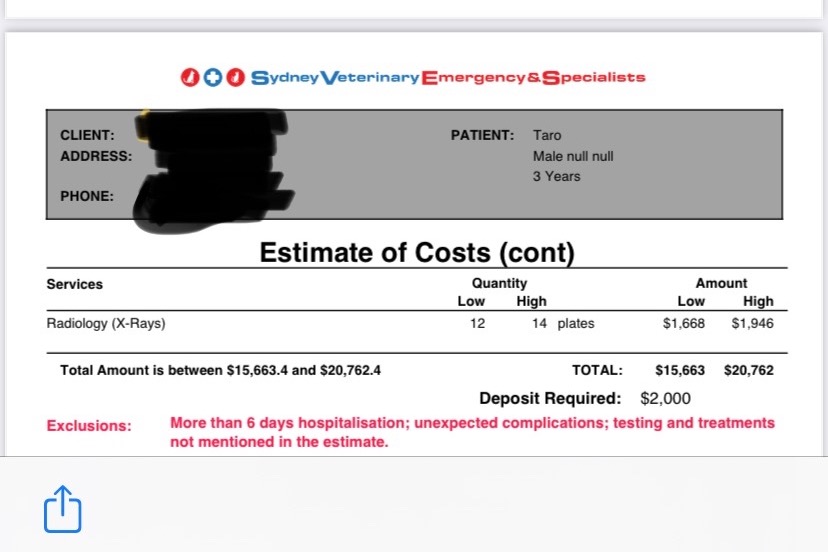

The surgeons at Sydney Vet Emergency & Specialists have said that the full cost of care and surgery will be about $15k-$20k. This amount is significant but at the same time pales in comparison to the possibility of losing an integral part of our family.

P.S For transparency, below is an estimate of costs for the medical procedures they sent to my boyfriend.